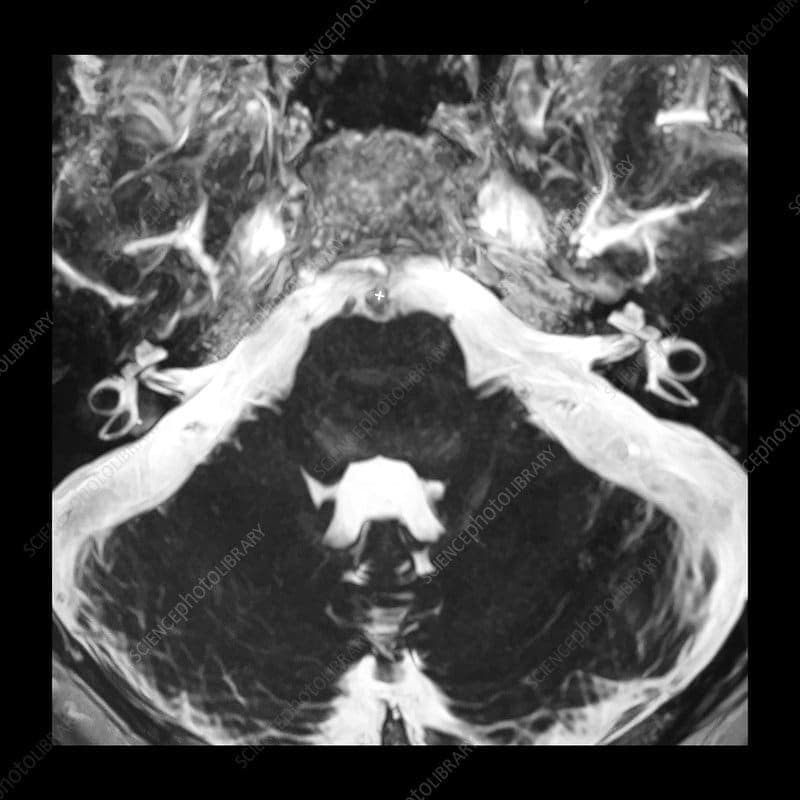

Inner Ear MRI (I.A.C MRI )

- Magnetic resonance imaging (MRI) scan:This test creates detailed images using a large magnet, a computer and radiofrequencies. Unlike computed tomography (CT or CAT) scans or X-rays, MRI does not use radiation.

- High-resolution images: MRI technology offers high-resolution images of the inner ear, providing detailed information that may not be achievable with other imaging modalities.

- Accurate diagnosis: An inner ear MRI can provide detailed images of the structures within the inner ear, allowing healthcare providers to accurately diagnose conditions such as vestibular disorders, Meniere’s disease, acoustic neuroma, and other ear-related issues.